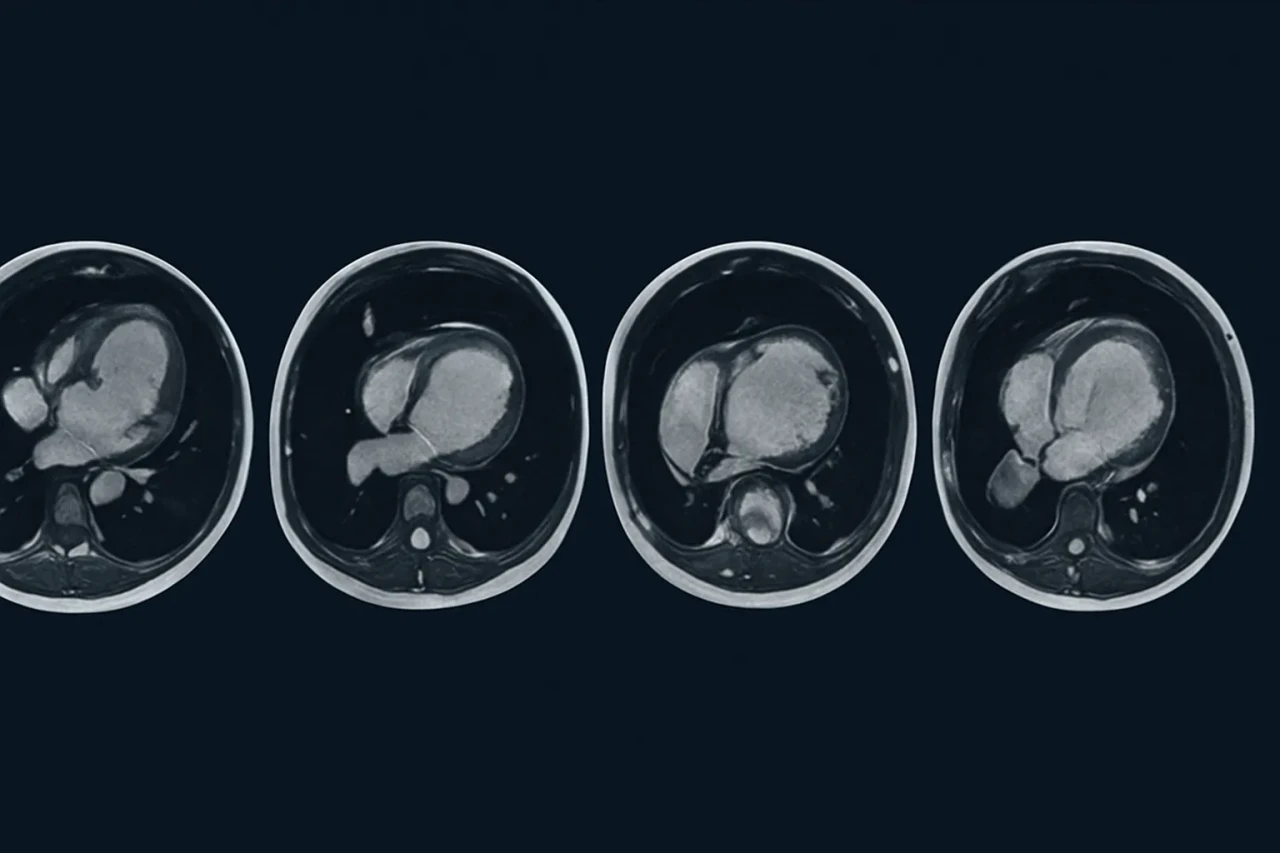

Sessiz tehlikeye karşı MRI umudu

Yapay zekâ destekli kalp MRI’ları, ölümcül kardiyomiyopati gibi hastalıkların teşhisinde devrim yaratıyor.

Cambridge Üniversitesi liderliğinde gerçekleştirilen araştırmada, yüz binlerce bireyin MRI kalp taramaları incelendi. Yapay zekâ destekli analiz yöntemleri kullanılarak kalp kaslarının kalınlığı ve yapısal bütünlüğü değerlendirildi. Elde edilen veriler, sessiz ilerleyen kardiyomiyopati gibi ciddi kalp hastalıklarının geleneksel yöntemlerle gözden kaçabileceğini, ancak MRI ile tespit edilebildiğini gösterdi.

Kardiyomiyopati Gibi Hastalıklar Artık Saklanamayacak

Kalp kasının zayıflaması ya da yapısal bozulmaya uğraması sonucu ortaya çıkan kardiyomiyopati, çoğu zaman sessiz seyreder. Fakat bu hastalık, ani kalp durmalarına kadar ilerleyebilir. MRI taramaları sayesinde kalp kaslarındaki küçük değişimler bile fark edilerek erken müdahale şansı doğuyor. Araştırma ayrıca kalp kasının kalınlaşma seviyesinin, kalp krizi ve ani ölüm riskleriyle doğrudan ilişkili olduğunu da ortaya koydu.